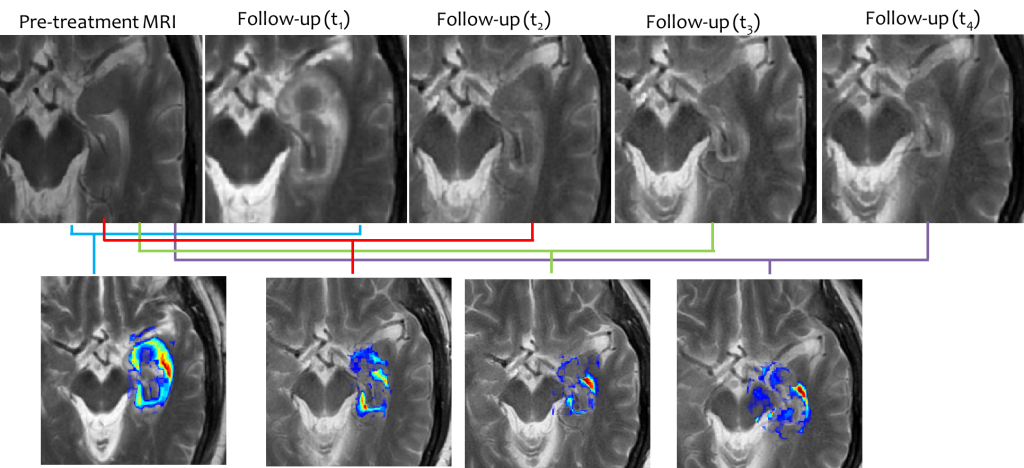

TREATMENT EVALUATION: Evaluating early response to treatment of neurological disorders

Currently post-treatment changes for evaluating patient’s response to treatment are monitored qualitatively via comparing volumetric changes of contrast enhancement on T1w MRI protocol acquired for follow-up (24-hours, 1-month, 3-months, 6-months post-treatment), with reference to pre-treatment T1w MRI (known as Recist criterion). Volumetric analysis provides a single global measurement of morphologic volume differences; and may not capture the local treatment effects (such as swelling, tissue necrosis) introduced due to treatment on and around the lesion. We have been working on developing a radiomic framework to evaluate early treatment related changes that may be better reflected via a voxel-by-voxel analysis of changes in MRI markers monitored over time. These per-voxel changes over time may provide cues about treatment-failure and serve as surrogate markers for evaluating patient’s response to treatment.